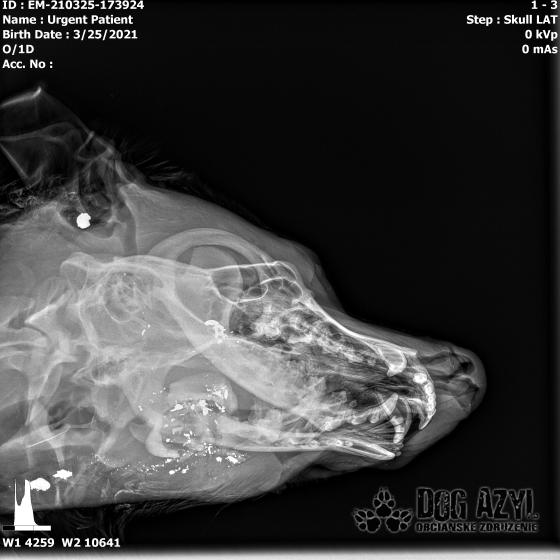

Strela zasiahla Barisa v oblasti lícnej kosti, ktorá mu rozdrvila sánku a následne putovala cez krk až po krčnú chrbticu. Úlomky z guľky (neviem ako sa to odborne volá) sa roztrieštili na "milión" kusov počas svojej cesty. Tieto úlomky sú všade (ako vidieť aj na RTG). Jeden (alebo niekoľko týchto úlomkov) sa dostali až po miechu, ale našťastie ju neprerazili. Toto spôsobilo, že Baris citlivosť v nohách na ľavej strane sice má, ale má poškodenú motoriku. Tieto úlomky sa z oblasti stavcov, miechy aj krku dnes odstránili, ale Barisko z ďaleka nemá vyhraté. Miecha je totiž zakrvácaná (opäť sa ospravedlňujem za nepresnosť a laickosť) a to, že ako veľmi je poškodená, alebo či jeho slabosť bola spôsobená "iba opuchom" sa ukáže cca do 24 hodín. Ak Baris nedajbože do zajtra stratí citlivosť v nohách, tak.. žiaľ... Ale! ak citlivosť zostane, prípadne nastane aj zlepšenie, tak vzplanie plamienok ďalšej nádeje a bojujeme ďalej!